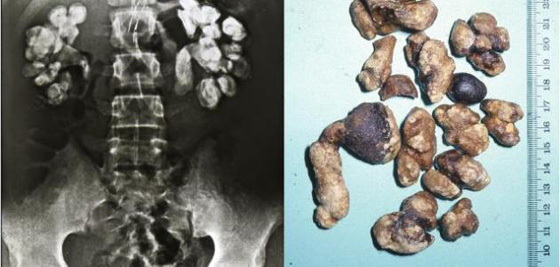

تشير النصوص اليونانية والرومانية والفارسية والهندية القديمة إلى عملية تعرف "بعملية تفتيت الحصاة المثانية"، لاستئصال الحصوة المتكونة في المثانة. خلال هذه العملية، يُطلب من المريض الاستلقاء على ظهره مباعداً بين ساقيه. وفي الأثناء، يتم تمرير شفرة في المثانة من خلال العجان، وهي المنطقة الملساء الواقعة بين كيس الصفن والشرج.

ومما يضفي طابعاً من الإهانة على هذه العملية، قيام الجراحين بإدخال أصابعهم أو أدواتهم الجراحية داخل المستقيم أو مجرى البول للمساعدة على إزالة الحصوة. وبالتالي، يترتب على هذه العملية شعور المريض بآلام مبرحة، علماً أن نسبة الوفاة تحت هذه العملية أو من مضاعفاتها قد تصل إلى 50%. بحلول القرن التاسع عشر، أخذ عدد عمليات تفتيت الحصاة المثانية في التراجع تدريجياً، حيث وقع استبدالها بطرق أكثر إنسانية. كما ساعدت الحميات الغذائية الصحية خلال القرن العشرين على جعل الإصابة بهذا الداء من الحالات الطبية النادرة.